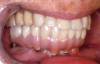

(3.) Prosthesis without access to the intaglio interface.

Figure 3

(4.) Intagilo inflammation of the soft tissue following removal of the prosthesis.

Figure 4

(5.) Prosthesis intaglio surface.

Figure 5

Several factors increasing the risk of peri-implantitis have been reported. Lack of access to the intaglio surface of the implant-supported prosthetics and poor oral hygiene of the implant is reported to increase the risk of peri-implantitis (Figure 3 through Figure 5). Concave intaglio design prevents oral hygiene access (Figure 6). Monje reported that 77.2% of the peri-implantitis cases had inadequate access for cleansability. 9 Serino and Ström found that 74% of the implants had no access to proper plaque control and highlighted the role of prosthesis design.10 Katafuchi suggested that a shallow emergence angle (EA) with a straight or concave transmucosal profile at the interproximal sites should be considered to minimize peri-implantitis risk for bone-level implant.11